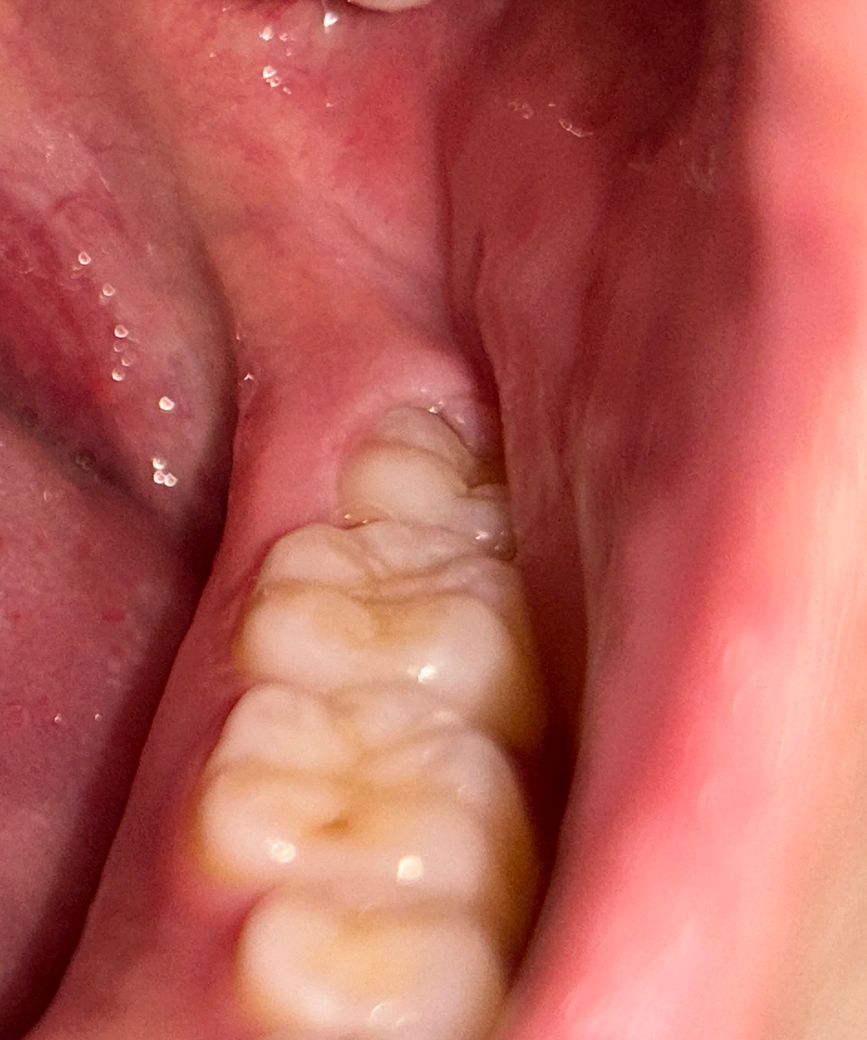

반만 나온 사랑니는 무조건 빼야할까요? ㅠㅠ..

• 양쪽 아랫 사랑니 방향이 올바르게 난건가요?

양 쪽 아랫 사랑니

• 1번 째 사진

사진으로 봤을 경우 치아는 정상적으로 올라오고 있는것으로 보입니다.

사랑니라고 해도 정상적으로 맹출이 되어 있다면 관리를 하면서 사용할수 있습니다.

사랑니가 지금처럼 난 경우에는 관리가 어려워 추후 문제가 될 수 잇습니다. 빼는 게 좋겠습니다.

지금은 어느정도 관리가 되고 잇지만 잇몸사이에 음식물이 들어가면서 관리가 안되면 염증이 자주 생길수 있습니다. 발치를 하시는게 좋을것같습니다.

현재 사랑니 방향이 비뚫어 나오는 것으로 보이며, 이 경우 앞의 어금니에 영향을 미칠수 있습니다. 따라서 인접 치아를 보호하기 위해서라도 발치를 하길 권장드립니다.